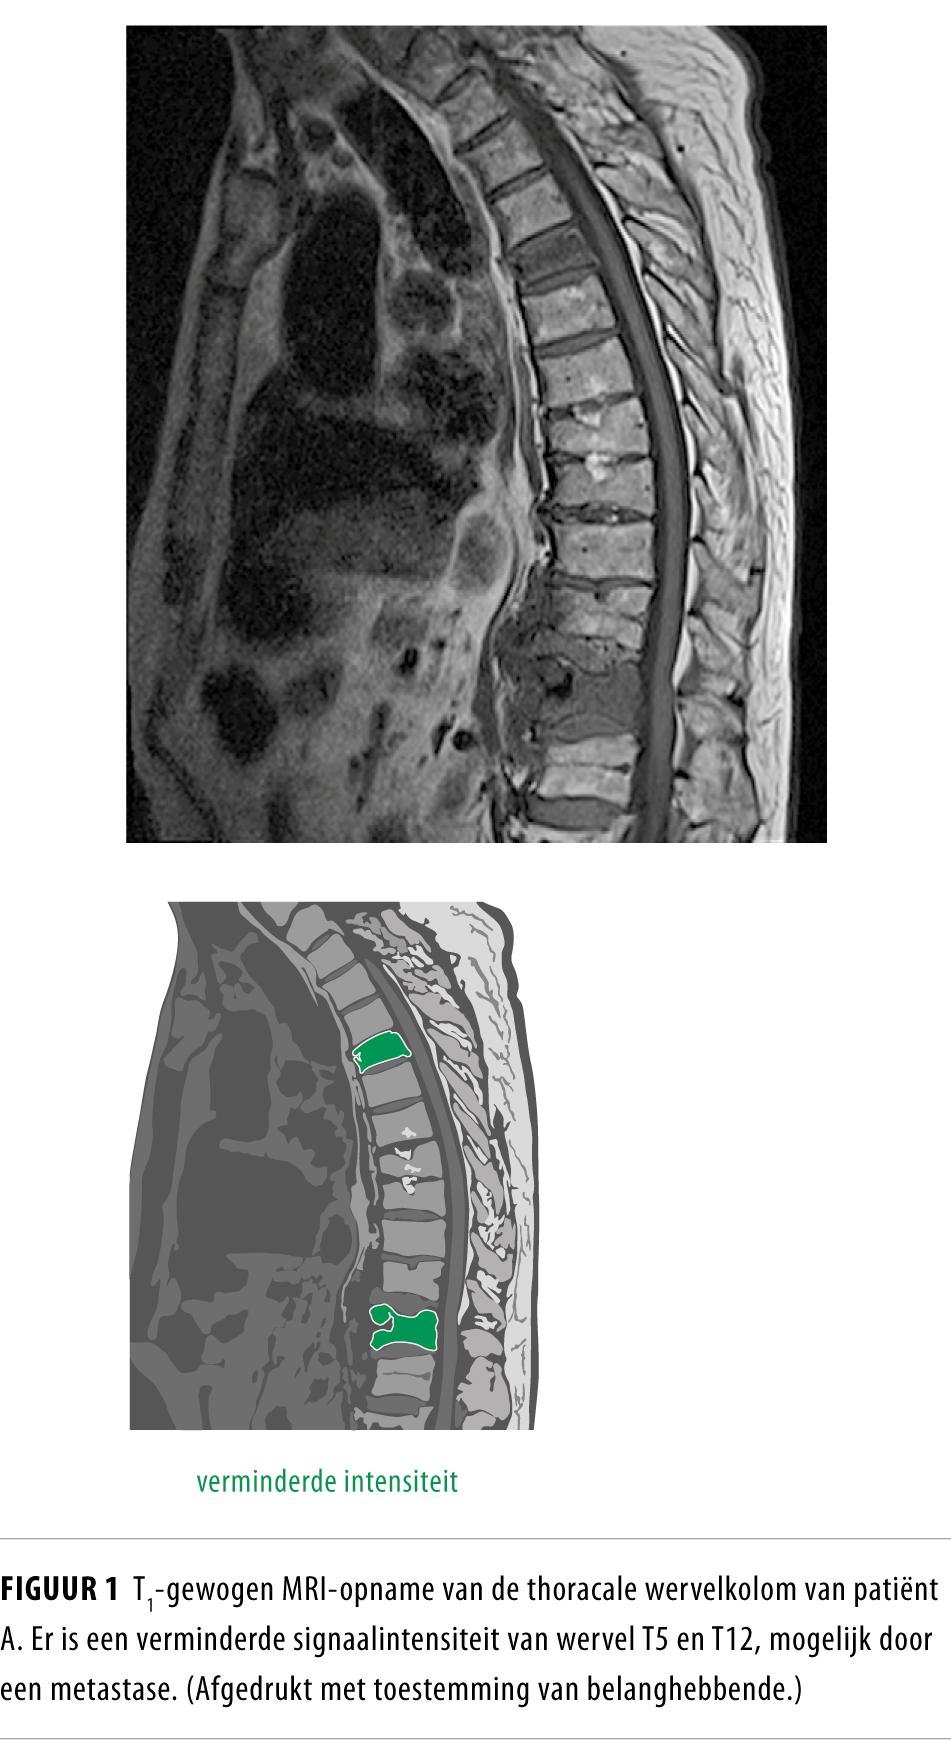

Patiënt knapte echter niet op. Hij werd delirant en de ontstekingswaarden stegen verder. Omdat patiënt tijdens zijn opname veel pijn in de rug en heupen ontwikkelde en krachtsverlies had in beide benen, werd een MRI van de lumbale wervelkolom verricht. Deze toonde spondylodiscitis op wervelniveau L4-L5 met wortelcompressie (figuur 3). De bloedkweken, afgenomen vóór aanvang van antibiotica, bleven negatief.